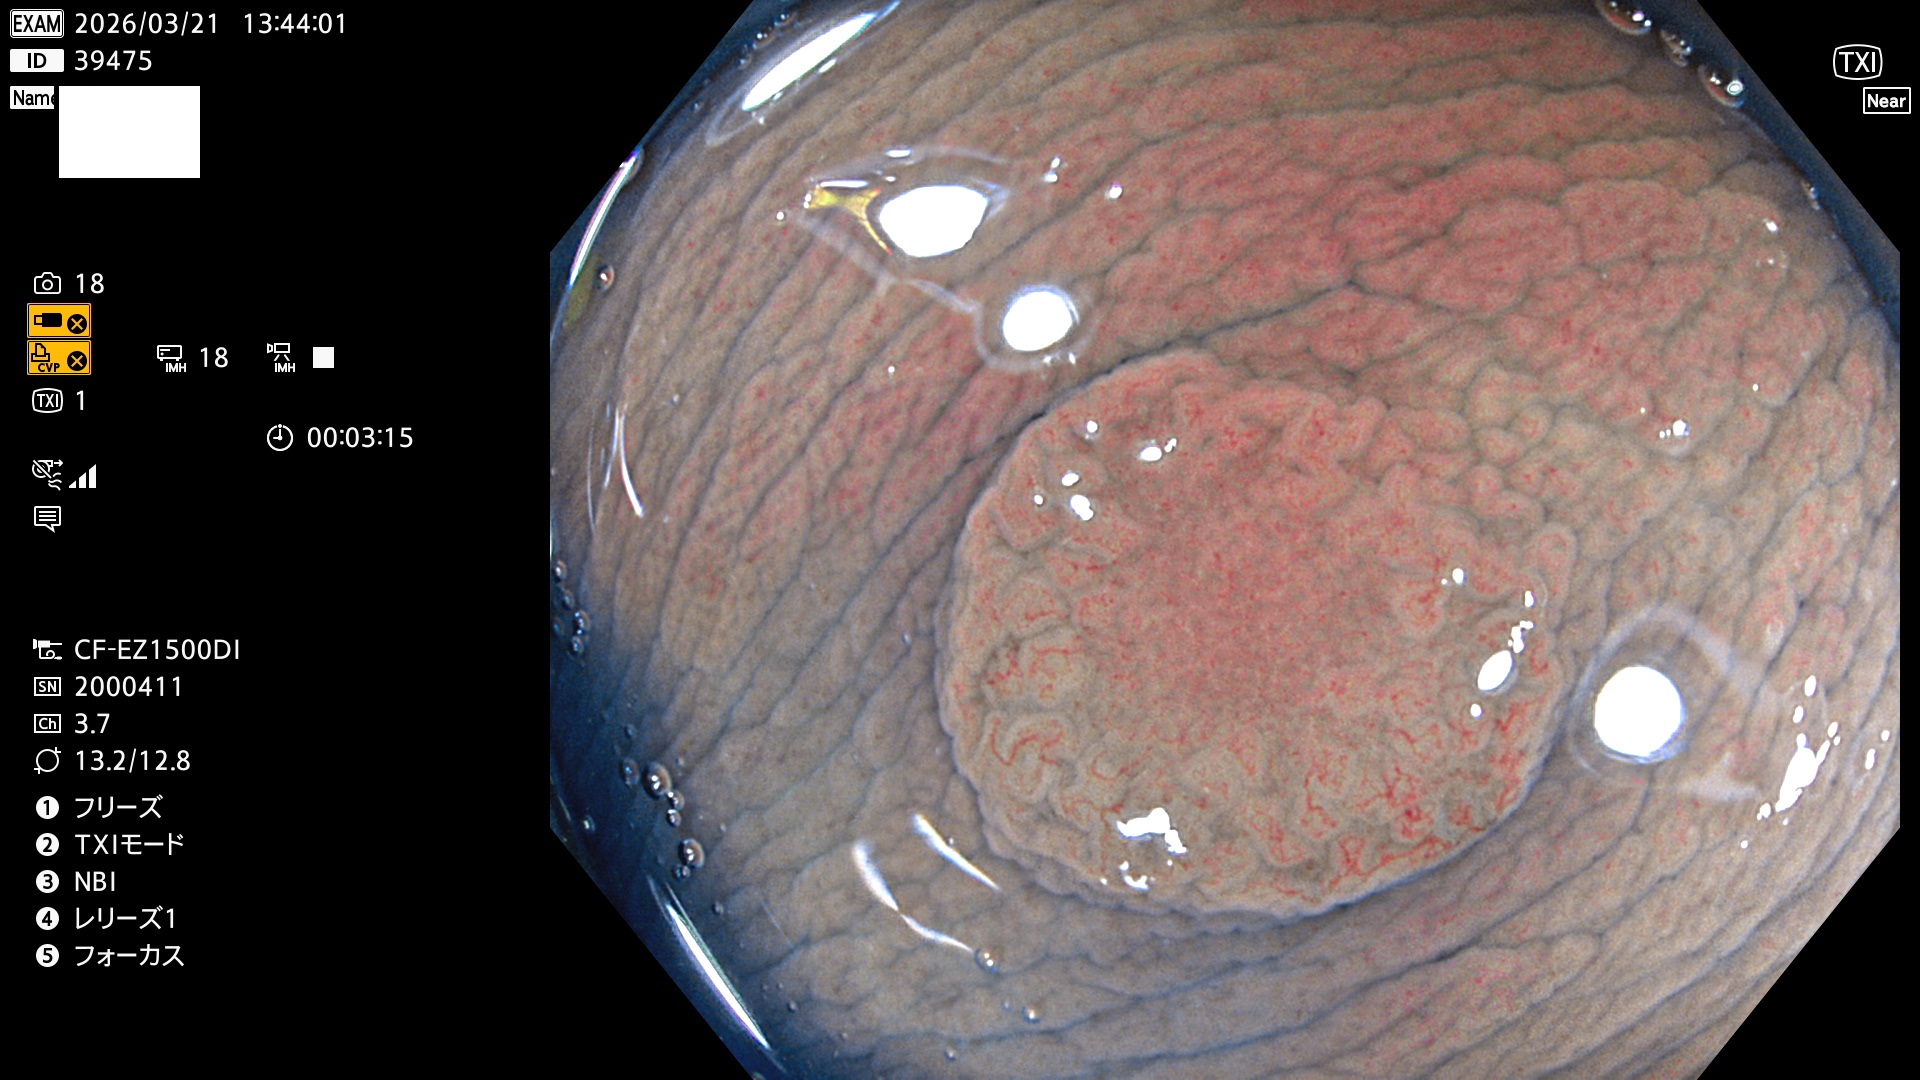

完全に平坦な物をUb、陥凹している物をUcと呼びます。Ubは認識が困難で、Ucはびらん(炎症)と紛らわしいために見落とされやすく、「内視鏡後・大腸癌」の原因になります。

毎週の検査(木・金・土・日)に発見されたUbとUc型・腺腫を、その週の日曜の夜にUPし1週間、提示します。

2026年3月19日〜3月22日の4日間(40件)4個 (Uc_ADR=4個/40人=10%)